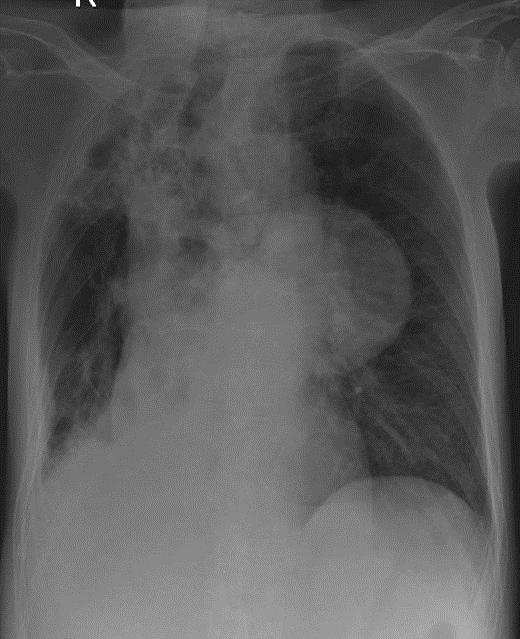

1-Khí quản lệch (P) 2-Xơ xẹp thùy trên phổi (P) 3-Thâm nhiểm phế nang thùy dưới phổi (P) => Viêm phổi 4-Dày dính màng phổi (P) 5-U trung thất (T)